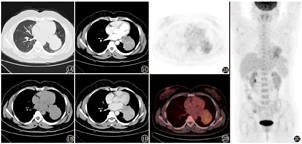

患者女,47岁,因"体格检查发现肺占位1个月余"就诊。CT(图1)示:左肺门旁类圆形肿块,内见"树枝"状钙化,增强后轻度略不均匀强化。实验室检查(括号内为正常参考值):糖类抗原(carbohydrate antigen, CA)125 109.2(0~35.0) kU/L,余指标未见明显异常。头体部18F-FDG PET/CT(德国Siemens Biograph Sensation 16型)显像(图2)示:左肺下叶近肺门旁见一肿块影,内伴线样钙化,大小约55 mm×74 mm,跨左肺斜裂生长,部分累及左肺上叶,FDG摄取中度增高,SUVmax为4.4;左肺门淋巴结肿大,FDG摄取未见增高。支气管镜示:左上舌支开口狭窄;左下基底支开口黏膜浸润隆起,开口狭窄。为明确诊断,行超声支气管镜检查,在左下基底支开口见一肿物,于肿物处行超声内镜引导下的经支气管针吸活组织检查术。病理示:光学显微镜下见黏膜组织内团巢样细胞生长、极破碎小组织内亦见少量神经内分泌细胞团巢;免疫组织化学检查:P40(-),细胞角蛋白(cytokeratin, CK)7(-),甲状腺转录因子-1 (thyroid transcription factor-1, TTF-1;-),新天冬氨酸蛋白酶A(Napsin A;-),CK5/6(-), Ventana(-),CD56(+),突触素(synaptophysin, Syn;-),嗜铬粒蛋白A (chromogranin A, CgA;-),细胞增殖核抗原Ki-67(<1%),诊断:(左下基底开口穿刺标本)弥漫型神经内分泌细胞增生或低级别神经内分泌肿瘤(类癌可能)。

综合各项检查后行手术治疗,术中探查显示肿块位于左下肺,大小约60 mm×80 mm,质硬,部分侵犯左上肺舌段肺组织;纵隔淋巴结多发肿大。术后常规病理示:光学显微镜下见肿瘤细胞呈梭形,束状、漩涡样排列,侵犯支气管壁(图3);免疫组织化学检查:广谱角蛋白[CK(pan);-](图4A),Ki-67(5%~10%;+),CD34(血管+),S-100(-),上皮膜抗原(epithelial membrane antigen, EMA;+;图4B),D2-40(+;图4C),CgA(-),Syn(-),生长抑素受体2(somatostatin receptor 2, SSTR2;+;图4D),P53(散在弱+),胶质纤维酸性蛋白(glial fibrillary acidic protein, GFAP;-),孕激素受体(progestogen receptor, PR;+;图4E),信号转导及转录激活蛋白6(signal transducer and activator of transcription 6, STAT6;-),结蛋白(Desmin;-),CD117(-),SOX10(-),SS18(BA)荧光原位杂交(fluorescence in situ hybridization, FISH;-),CD10(-),诊断为脑膜瘤,无淋巴结转移。PET/CT及MR显像提示中枢系统未发现脑膜瘤,遂诊断为肺原发性脑膜瘤(primary pulmonary meningioma, PPM)。术后半年随访未见复发。

目前认为PPM女性发病偏多,40~60岁为好发年龄,多数无临床症状,少数因瘤体较大出现咳嗽,或累犯邻近血管引起咯血。文献报道PPM多为肺外周实性孤立性结节,部分为磨玻璃密度结节或钙化结节[6],少数为双肺多发结节[7];与中枢神经系统脑膜瘤明显强化不同,PPM表现为不同形式的强化[8]。国内外仅报道了10例有18F-FDG PET/CT影像资料的PPM病例,包括14枚病灶(2枚病灶2例,3枚病灶1例,1例双肺多发结节但仅1枚明确为PPM)[9]。病灶大小为9.6~60 mm,摄取值从无增高至SUVmax12.9。PPM一般为良性肿瘤,仅Cimini等[10]报道了1枚病灶为恶性,大小为12 mm,SUVmax为2.46,尚不能表明FDG摄取与PPM大小及良恶性的关系。PPM多表现为实性结节或肿块,密度均匀,边界光滑,FDG分布均匀;病灶可表现为中央区摄取较高,与其他较大肺内肿块出现中央坏死外周实性成分FDG摄取较高不同,这可能与其恶性程度较低、增殖缓慢且速度不一、血供分布不均有关。本例患者为47岁女性,体格检查发现肺占位,表现为近肺门的类圆形肿块,跨叶生长,内见"树枝"状钙化,大小约60 mm×80 mm,呈轻度略不均匀强化,FDG摄取中度增高,SUVmax为4.4。